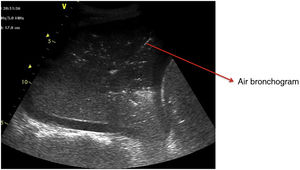

Pattern C: this is characterized by the “tissue-like sign” or “shred sign”. In the “tissue-like sign”, the echogenicity of the consolidated lung parenchyma is similar to that of the liver. Within the consolidated component we can visualize hyperechogenic images corresponding to the air bronchogram (Fig. 5). The “shred sign” in turn consists of consolidations of smaller size manifesting as a disruption of the pleural line, with an irregular or serrated margin that separates the consolidated component from the aerated lung (Fig. 6) (Video 6).5